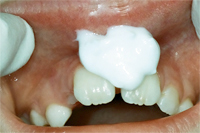

Die Abb. 1 bis 4 sollen als anschauliche Beispiele für gesunde und kranke Fundamente dienen.

Ein 31 Jahre alter Patient zeigt einen starke Zahnfleisch-Rückgang im Oberkiefer (Abb. 1 und 3) und wir beschliessen, diese Rezessionen zu behandeln.